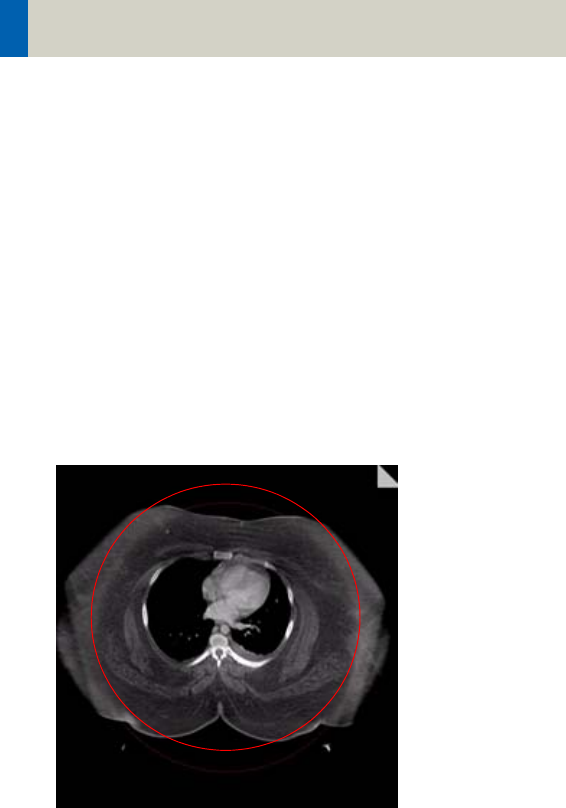

Positioning

rately to ensure a centered location of the skull.

correct positioning wrong positioning

of the head of the head

For trauma examinations of the head we provide two

protocols, to be found in the specials folder:

– HeadTrauma

– HeadTraumaSeq.

The scan protocols enable you to utilize the full 50 cm

FoV, resulting in easier patient positioning for trauma

examinations and to ensure the highest performance,

the dedicated PFO head filter is not used.